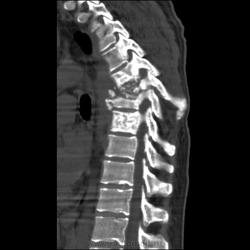

Молодой человек около 30 лет. Из анамнеза известно, что в мае этого года поступает в п\п с диагнозом двухсторонней пневмонией, после дообледования направили в туб. диспансер, к сожалению первых снимков не нашел, есть архив КТ.

Поставил:Туберкулезный спондилит, патологический перелом.

Такая картина сейчас:

Раиль, получается, что сначала появился натечник, а потом разрушился позвонок... Так? Я бы на первое место поставила сепсис, гематогенный (если не контактный...) гнойный спондилит, склеротические поражения позвонков выше и ниже патологического перелома тоже не подходят для туб.спондилита. По КТ не могу исключить сочетание с туберкулезом, но такое количество мелких и средних полостей, преимущественно субплеврально, более характерно для септических эмболов. Есть ли данные по клинике, анализам крови, мокроты? Есть ли динамика самих полостей? Для септических эмболов характерна быстрая динамика с образованием тонкостенной полости. ВИЧ? Подождём еще мнений, может, я не права.

Спондилит есть, да, с патологическим переломом, но вряд ли туберкулезный. А в легких - септическая эмболия. Пациент не наркоман, часом? Вообще, социальный тип?

А. натечник не хилый...